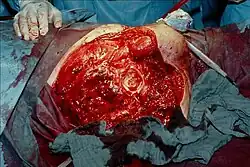

| Photograph before right leg amputation (hemipelvectomy) of a patient with gas gangrene. The right thigh is edematous (swollen) and discoloured with necrotic bullae (large blisters). Crepitation is detected on deep palpation. At this juncture, the patient is in shock, and died less than eight hours later. | |

Hemipelvectomy for gas gangrene

Hemipelvectomy for gas gangrene -